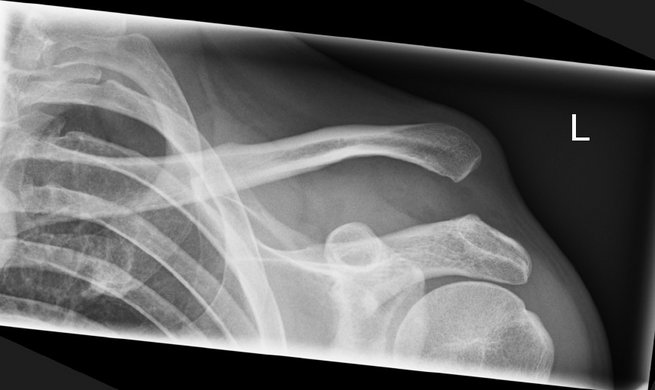

Eine AC-Gelenksprengung ist eine Verletzung des Schultereckgelenks (Akromioklavikulargelenks), meist nach einem Sturz direkt auf die Schulterspitze. Dabei zerreißen – je nach Schweregrad – die Bandverbindungen zwischen Schlüsselbein und Schulterblatt (AC- und/oder CC-Bänder). Typisch sind eine sichtbare Stufe über dem Schultereckgelenk („Klaviertastenphänomen“) und Bewegungsschmerzen bei Armhebung.

Leichte Formen (Rockwood I–II) werden konservativ behandelt, meist mit Ruhigstellung und frühzeitiger Mobilisierung.

Höhere Grade (III–V, selten VI) erfordern häufig eine operative Stabilisierung, insbesondere bei jungen, aktiven oder sportlich ambitionierten Patientinnen und Patienten.